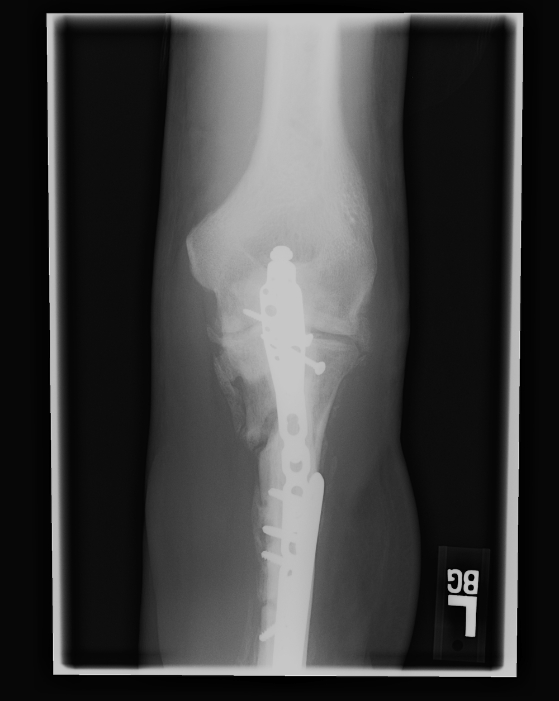

Nov 23, 2007 These pictures were taken in Iraq or possibly in Germany. The stabilizing bars have been attached above his elbow and about half way down his forearm. You can see the bone chips scattered around in his upper forearm. |